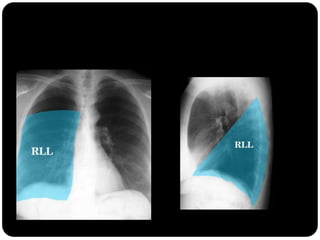

Atelectasia lobo

inferior direito

Observar:

Atelectasias de lobos

inferiores deslocam

o hilo posterior e

medialmente;